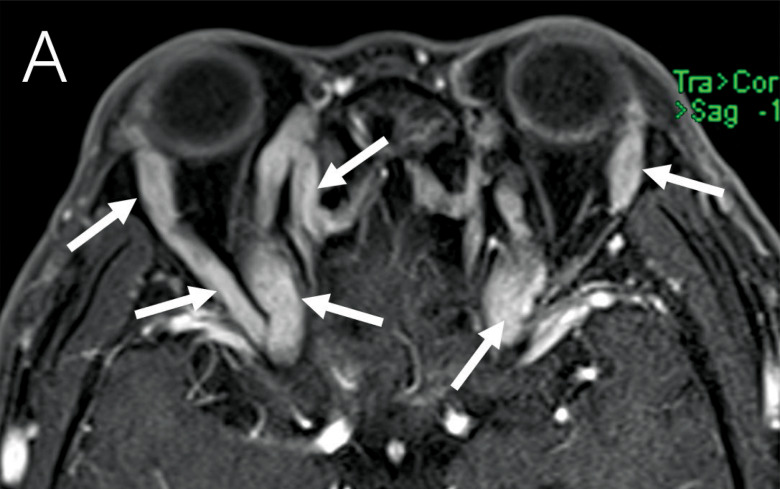

教学要点:免疫球蛋白G4相关性眼病(IgG4 - ROD)可能仅表现为三叉神经眶支弥漫性增厚。

Teaching point: Immunoglobulin G4‑related ophthalmic disease (IgG4‑ROD) may present only as diffuse thickening of the orbital branches of the trigeminal nerve.